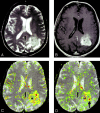

Background and purpose: Relative cerebral blood volume (rCBV) and vascular permeability (K(trans)) permit in vivo assessment of glioma microvasculature. We assessed the associations between rCBV and K(trans) derived from dynamic, susceptibility-weighted, contrast-enhanced (DSC) MR imaging and tumor grade and between rCBV and K(trans).

Methods: Seventy-three patients with primary gliomas underwent conventional and DSC MR imaging. rCBVs were obtained from regions of maximal abnormality for each lesion on rCBV color maps. K(trans) was derived from a pharmacokinetic modeling algorithm. Histopathologic grade was compared with rCBV and K(trans) (Tukey honestly significant difference). Spearman and Pearson correlation factors were determined between rCBV, K(trans), and tumor grade. The diagnostic utility of rCBV and K(trans) in discriminating grade II or III tumors from grade I tumors was assessed by logistic regression.

Results: rCBV was significantly different for all three grades (P </=.0005). K(trans) was significantly different between grade I and grade II or III (P =.027) but not between other grades or combinations of grades. Spearman rank and Pearson correlations, respectively, were as follows: rCBV and grade, r = 0.817 and r = 0.771; K(trans) and grade, r = 0.234 and r = 0.277; and rCBV and K(trans), r = 0.266 and r = 0.163. Only rCBV was significantly predictive of high-grade gliomas (P <.0001).

Conclusion: rCBV with strongly correlated with tumor grade; the correlation between K(trans) and tumor grade was weaker. rCBV and K(trans) were positively but weakly correlated, suggesting that these parameters demonstrate different tumor characteristics. rCBV is a more significant predictor of high-grade glioma than K(trans).